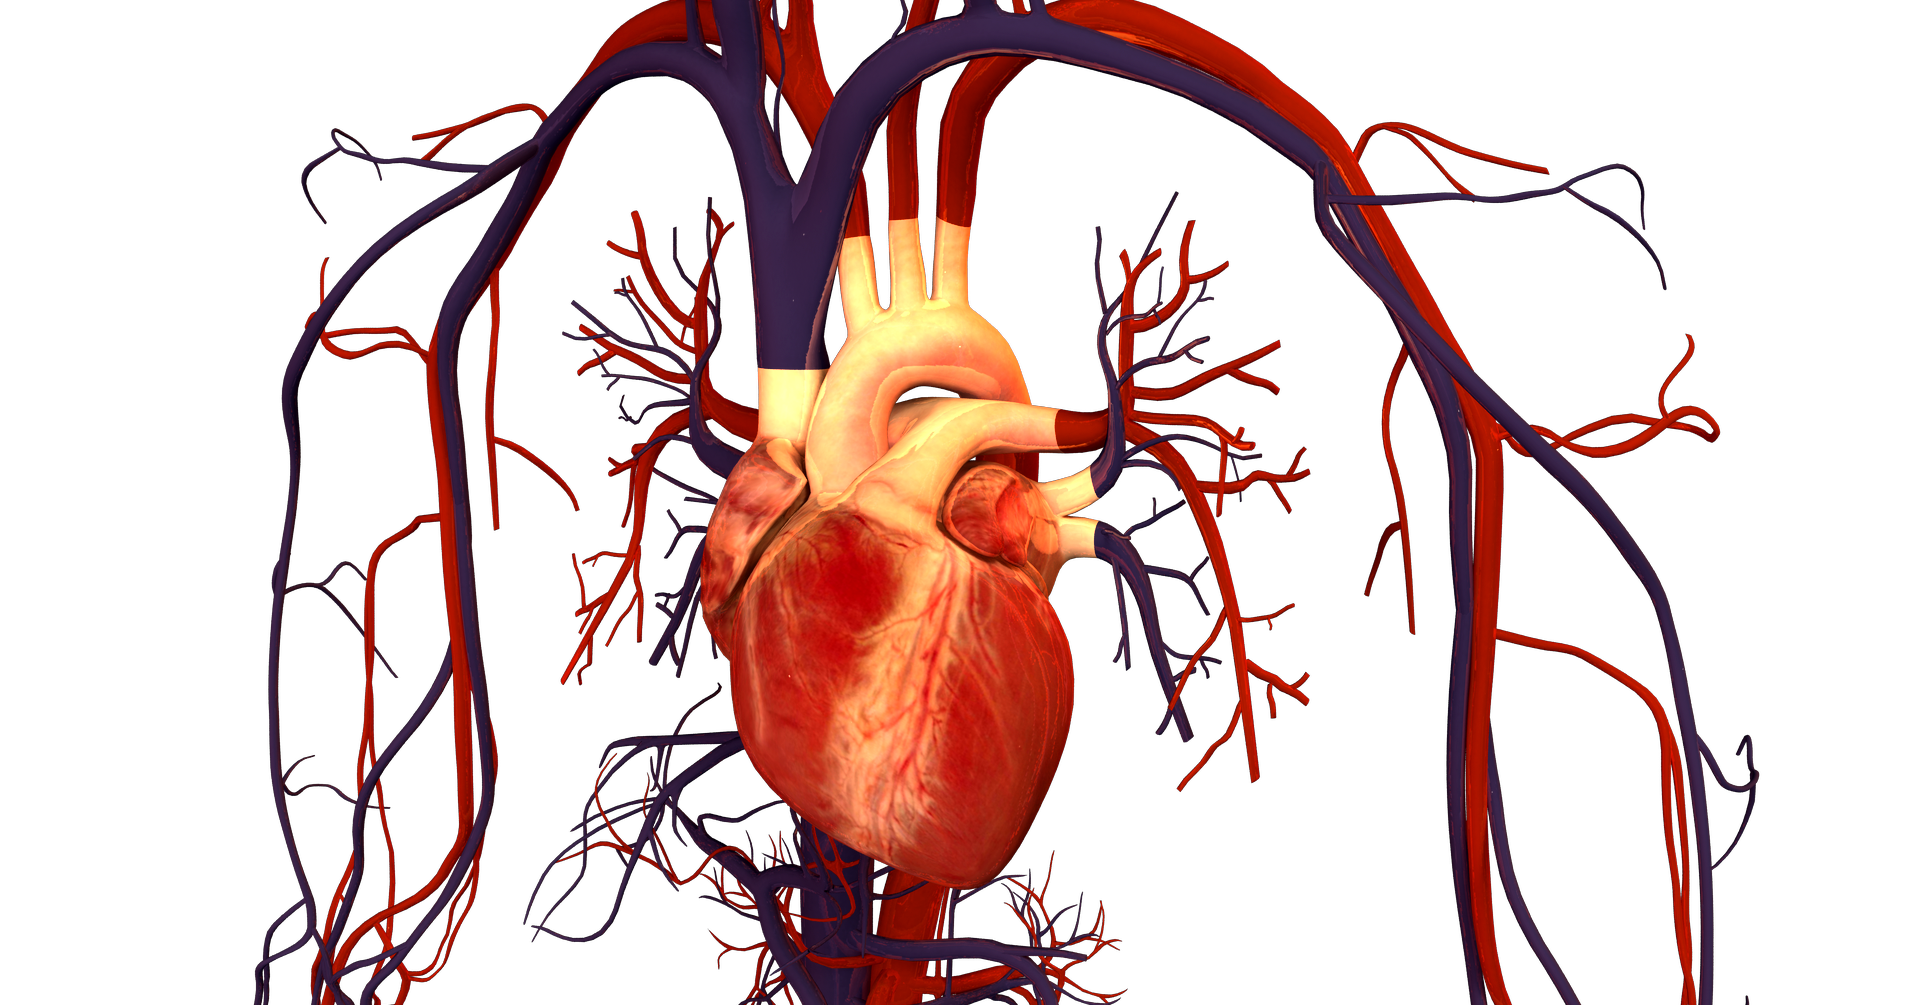

Dødeligheten av hjerte- og karsykdommer er betydelig redusert siden 1970-årene. Det skyldes at færre røyker, at man spiser sunnere, at nivåene av blodtrykk og kolesterol har gått ned og at behandlingen er blitt bedre.

Hjerte- og karsykdommer var lenge den sykdomsgruppen som førte til flest dødsfall, men siden 2017 har kreft vært den hyppigste dødsårsaken i Norge. I dette seminaret setter vi søkelyset på denne utviklingen.